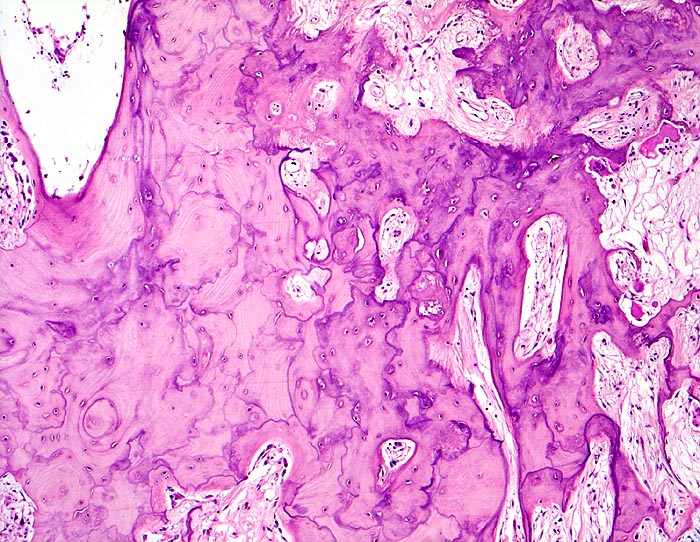

An den betroffenen Stellen ist sowohl der Knochenabbau als auch der Knochenanbau gesteigert. Die Osteoklasten sind auffallend gross und enthalten sehr viele Kerne (> 3518). Die aktivierten Osteoblasten produzieren verdickte und grob geflochtene Spongiosabälkchen. Der neugebildete Knochen ist strukturell und morphologisch abnorm und schlecht mineralisiert. Der Knochen wird dadurch weich und anfällig auf Frakturen oder Deformation unter Belastung (nach vorne gebogene Säbelscheidentibia). Das Knochenmark wird ersetzt durch fibrovaskuläres lockeres Stroma, welches an Granulationsgewebe erinnert. Mikroskopisch werden eine osteolytische Initialphase, eine Umbauphase mit verstärkter Knochenneubildung und eine sklerosierende Stabilisationsphase mit strukturellem Umbau und Spongiosierung der Kortikalis (verbreiterte spongiosaartige Kortikalis) unterschieden.

• Die Spongiosabälkchen sind auffallend verdickt, vermehrt und unregelmässig geformt.

• Prominente Zementlinien sind mosaikartig angeordnet.